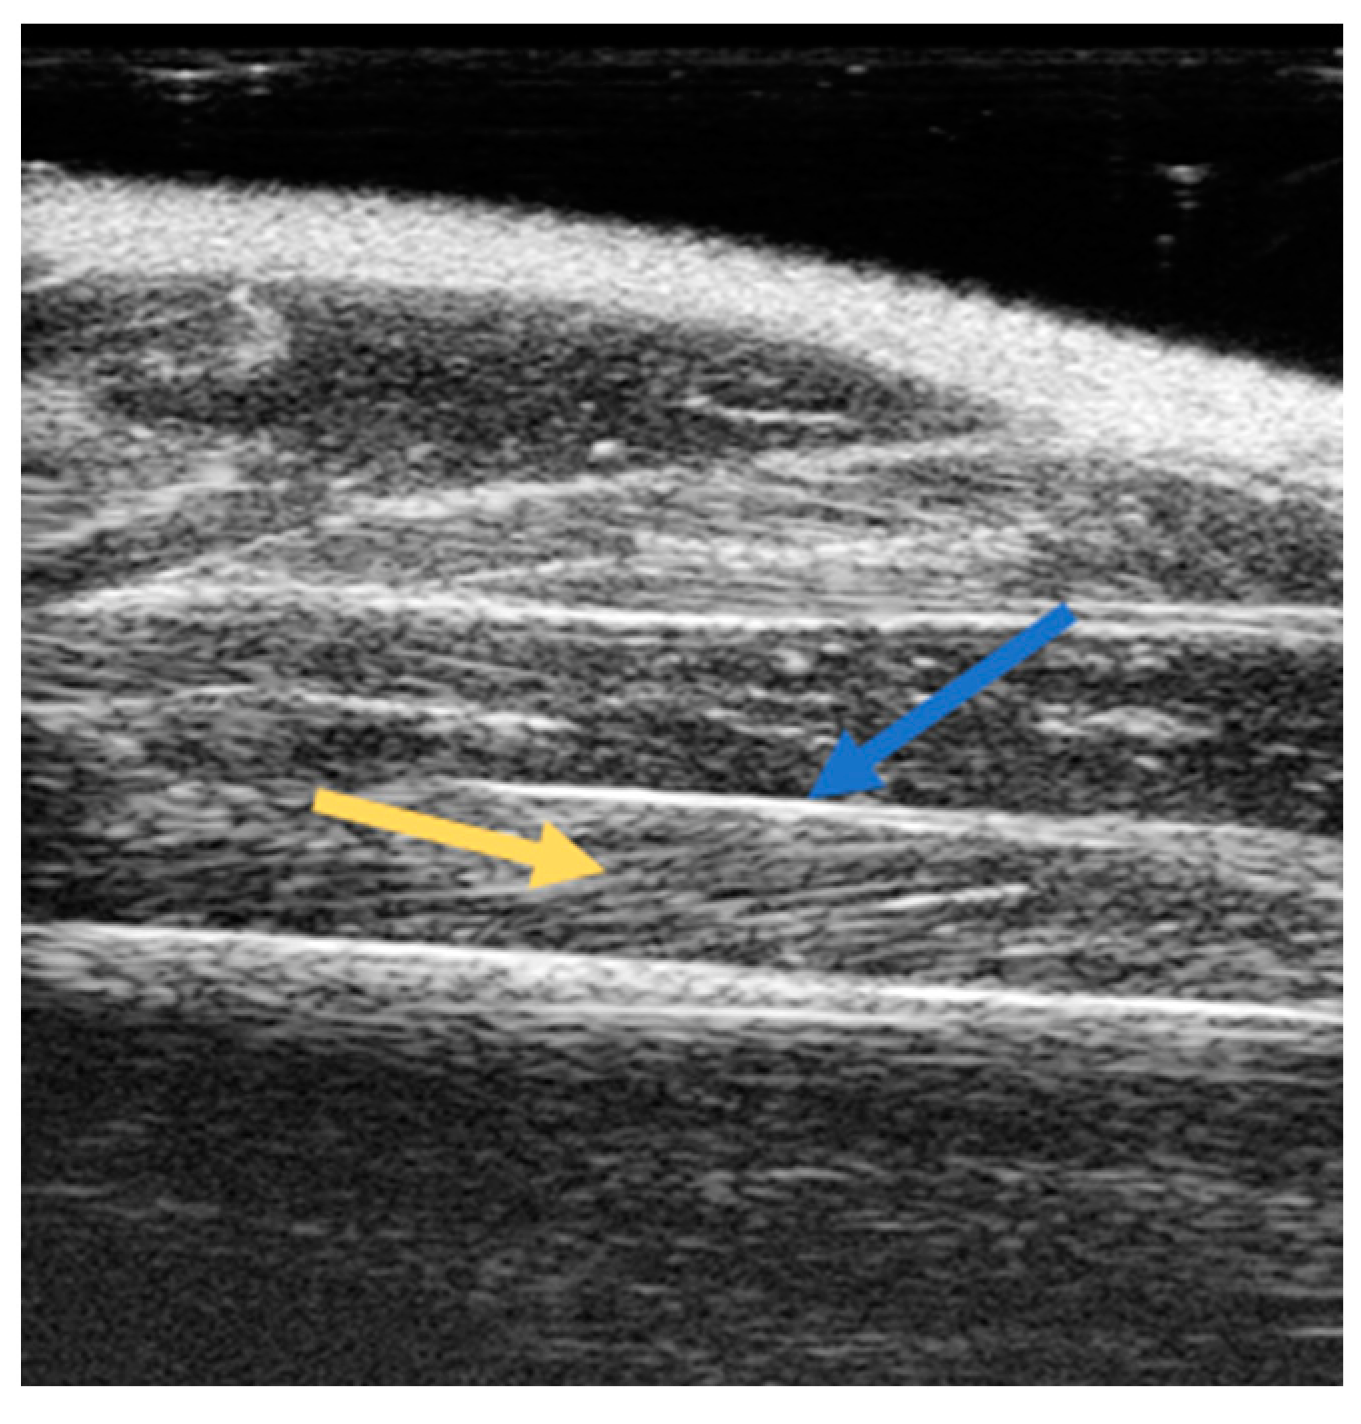

| Vevo 770 (VisualSonics, Toronto, ON, Canada) 40 MHz | GAS, SOL | Rat in ventral decubitus position with the ankle immobilized in full extension. Longitudinal acquisitions | PA, MT | [22] |

| Vevo 770 (VisualSonics, Toronto, ON, Canada) 40 MHz | GAS | Rat in ventral decubitus position with the ankle immobilized in an angle of 90°. Longitudinal acquisitions | PA, MT | [25] |

| Vevo 2100 (VisualSonics, Toronto, ON, Canada) 40 MHz | GAS, SOL | Rat in ventral decubitus position, with the hind limbs parallel to the body and with the foot forming an angle of 90° with respect to the hind limb, placing the probe parallel to the longitudinal muscle axis | Volume | [23] |